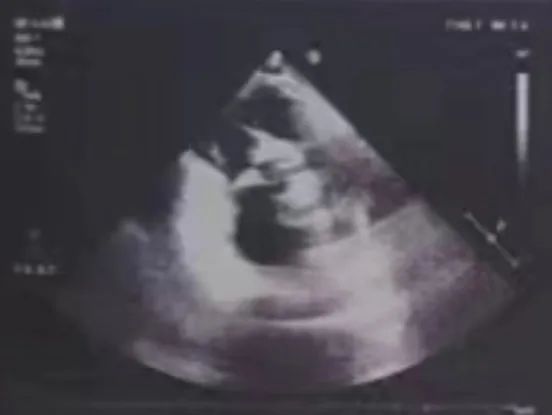

心脏超声

• Type 0型二叶瓣;

• 主动脉瓣重度狭窄伴轻度反流;

• 二、三尖瓣中度反流;

• 心包腔微少量积液;

• 肺动脉高压;

• 左室收缩功能减低;

• 左房增大,升主动脉内径增宽;

• 主动脉瓣明显钙化,结构模糊,开放受限,关闭欠佳;

• LVEF: 40%;

• 左室舒张末期内径(LVD):5.5 cm;

• 主动脉瓣瓣口峰值流速:5.1m/s;平均跨瓣压差:50mmHg;最大跨瓣压差:104mmHg。